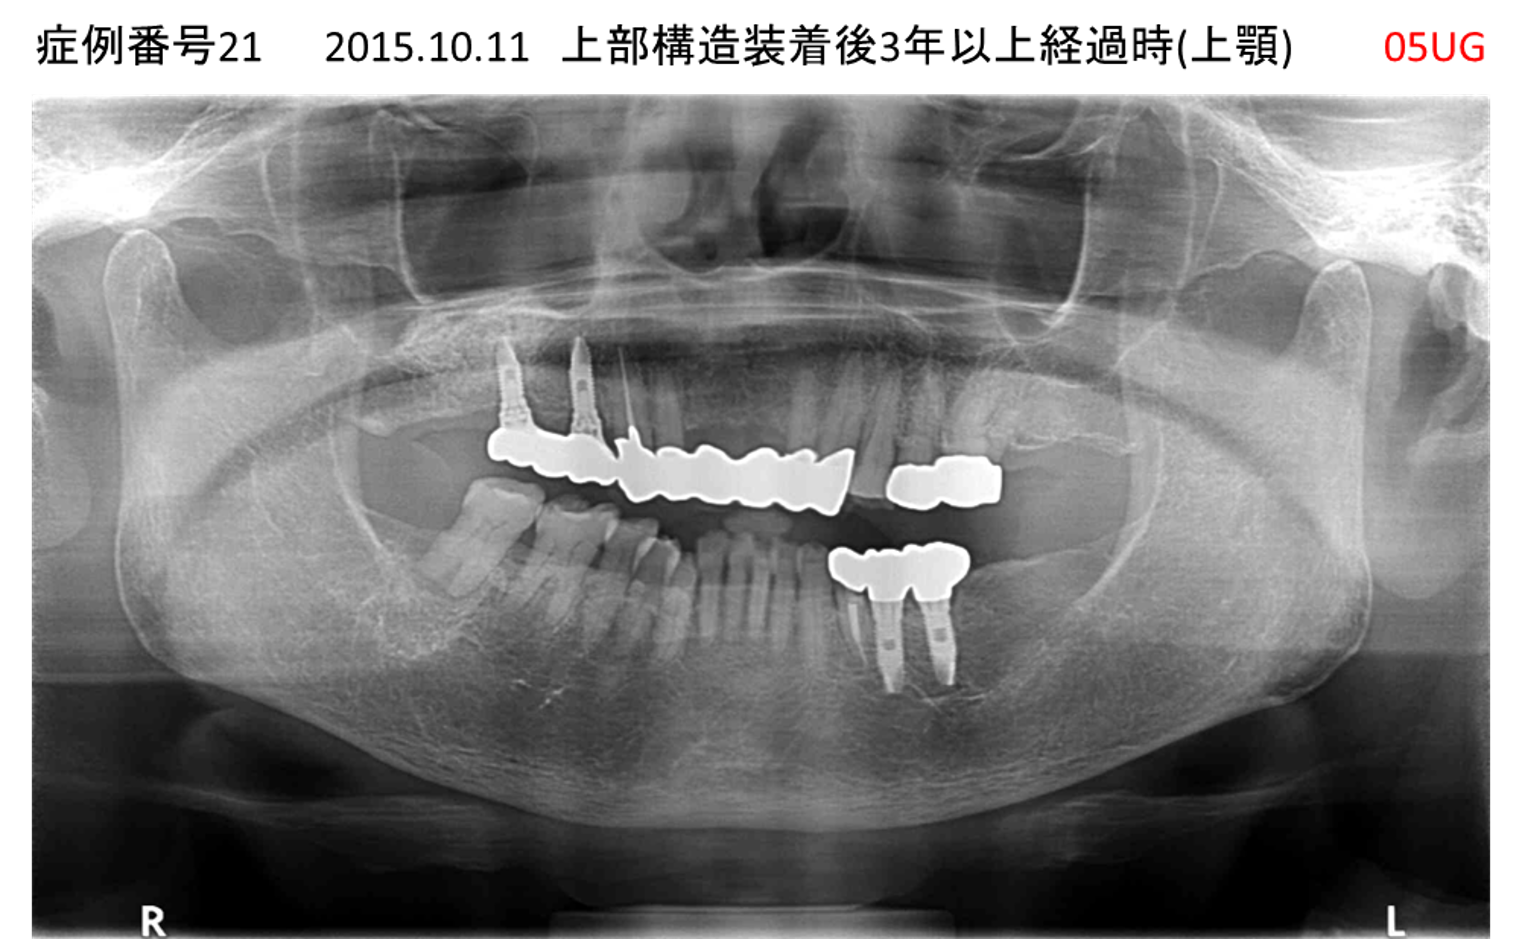

義歯が合わない、噛めない患者様のインプラント症例

| 治療名称 |

インプラントコーヌステレスコープ |

| 治療費用 |

270万円+税 |

| 治療期間 |

4か月 |

| 患者さんの症状(主訴) |

義歯が合わない、噛めない |

| 治療内容 |

インプラント、義歯作製(コーヌステレスコープ) |

| 治療結果 |

しっかり噛めるようになった。見栄えが良くなった。 |

| 治療の注意点(リスク/副作用) |

義歯が壊れた場合、インプラントが壊れた場合は再治療が必要 |